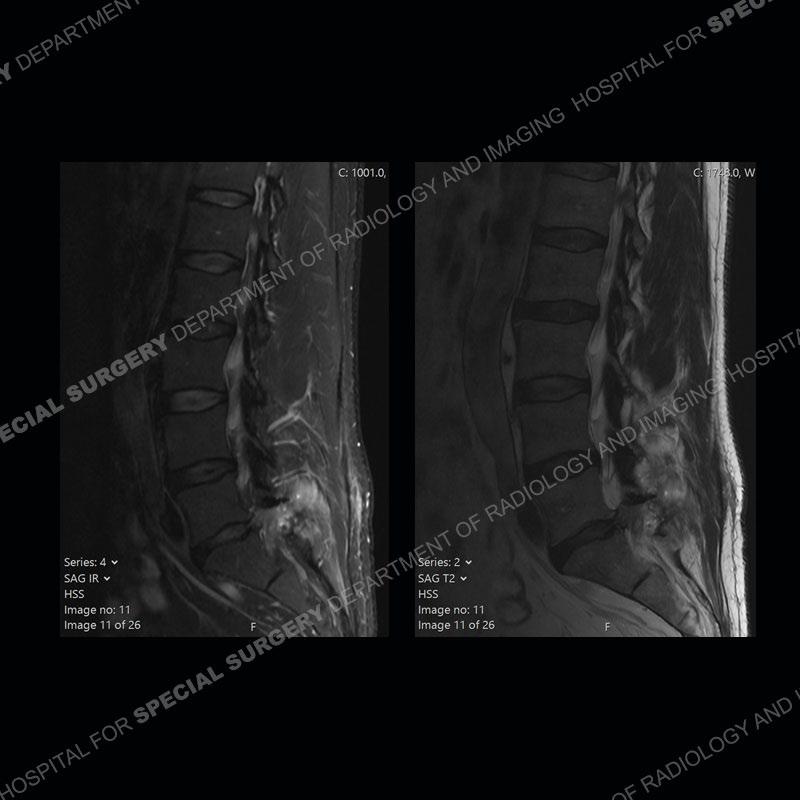

Post operative changes are seen on the left side at L5-S1 where there is near complete removal of the left sided L5 lamina, partial resection of the left L5-S1 facet joint, and resection of the left sided ligamentum flavum. In the anterolateral epidural space about the subarticular recess is a mass that demonstrates similar T1 and T2 signal characteristics to the adjacent degenerated disc. There is enhancement about the periphery of the mass, but the majority of this somewhat geographic or polyploid mass demonstrates no enhancement. The mass exerts prominent mass effect on the left S1 axillary sleeve/proximal nerve root. The left S1 nerve root shows enlargement and increased enhancement as compared to the contralateral right side.

Diagnosis: Recurrent Disc Herniation

Not as much of a diagnostic dilemma as some other cases but more so just a very nice example of what can be a difficult assessment at times. The evaluation of granulation tissue/scar/epidural fibrosis vs. disc herniation particularly in the earlier post operative period can be very difficult. Clues that can assist in identifying a disc herniation are a more geographic or polypoid nature to the mass, signal characteristics similar to the adjacent degenerated disc, mass effect upon the thecal sac/adjacent neural structures, and a typical enhancement pattern. As the disc material is avascular, as long as imaging is performed in a relatively rapid fashion after contrast administration (within 20-30 minutes), the granulation tissue around the disc will enhance but the disc material itself will not. If there is a marked delay between contrast administration and imaging, there may be diffusion of contrast into the disc making the assessment very difficult. The marked utility of contrast to help delineate disc vs. scar has led to our institution employing contrast fairly uniformly within the first two years following surgery.

The scar tissue in the setting of prior disc removal will be present in the anterior and anteriorlateral aspect of the epidural space. The signal characteristics can be somewhat variable from slightly more T2 hyperintense earlier on to T2 hypointense as the scar matures. However, the signal does not tend to follow the adjacent degenerated disc. The scar can produce mass effect, but it does not have to do so. In addition, at times the scar may be associated with a retraction of the adjacent thecal sac. Given the vascular nature of the scar there is typically somewhat avid, uniform enhancement which occurs fairly rapidly after contrast administration and begins to diminish within 20 minutes or so. Trying to discern the difference between scar and disc is of paramount importance given the rather poor outcomes associated with resection of scar as compared to disc material.